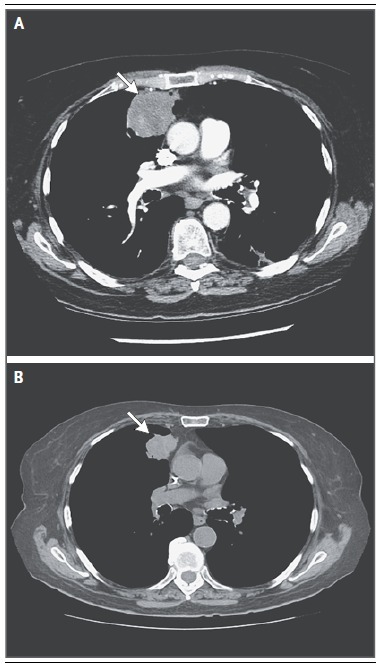

研究病例发现,定义原发灶不明的转移癌的组织来源既带来了希望也提出了挑战(图 3 和图 4)。免疫组化结果能够确定肿瘤来源的患者约占所有原发灶不明的转移癌患者的 25%。例如甲状腺转录因子 1(TTF1)阳性,细胞角蛋白 7(CK7)阳性提示肺癌来源,细胞角蛋白 20 阳性,同源蛋白 CDX-2 阳性和 CK7 阴性提示消化道肿瘤来源,GCDFP ( 多囊肿疾病流体蛋白)-15 阳性或乳腺珠蛋白阳性,CK7 阳性提示乳腺癌来源。一般来说,肿瘤的播散类型支持免疫组化的结果,有时,免疫组化的结果与影像学检查不一致(图 3A 和 3B)。

图 3 评价原发灶不明的转移癌时影像学发现与免疫组化结果不一致患者 77 岁,女性,无吸烟史,肺炎随访时胸部发现肺右上叶一 5.7 厘米的肿块,侵及右中叶和裂隙(图 A,箭头)。取肿块活检发现中分化腺癌,伴同源蛋白质 CDX-2,CK20,癌胚抗原强阳性,CK7 和 TTF1 阴性。病理报告结果提示下消化道肿瘤来源,包括阑尾和结直肠。上消化道内镜检查和结肠镜检查均未见异常。无明确证据提示小肠和阑尾肿瘤来源。术前短期氟尿嘧啶和奥沙利铂化疗后,患者手术切除肺部肿块(图 B,箭头)。术后病理报告结果不变(假设结直肠癌转移),术后按原方案化疗。术后结肠镜检查结果阴性。患者入组微小 RNA 组织来源分子分析临床试验证实结肠肿瘤来源。尽管化疗能否使该类患者获益还未知,临床医生制定治疗方案时应考虑病理结果。结肠癌来源原发灶不明的转移癌最常表现为孤立转移和卵巢转移。